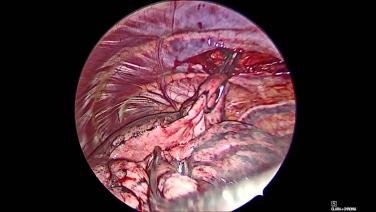

VATS Lobectomy Using HARMONIC™ 1100 Shears, ECHELON FLEX™ Powered Vascular Stapler, and SURGICEL™ Absorbable Hemostat